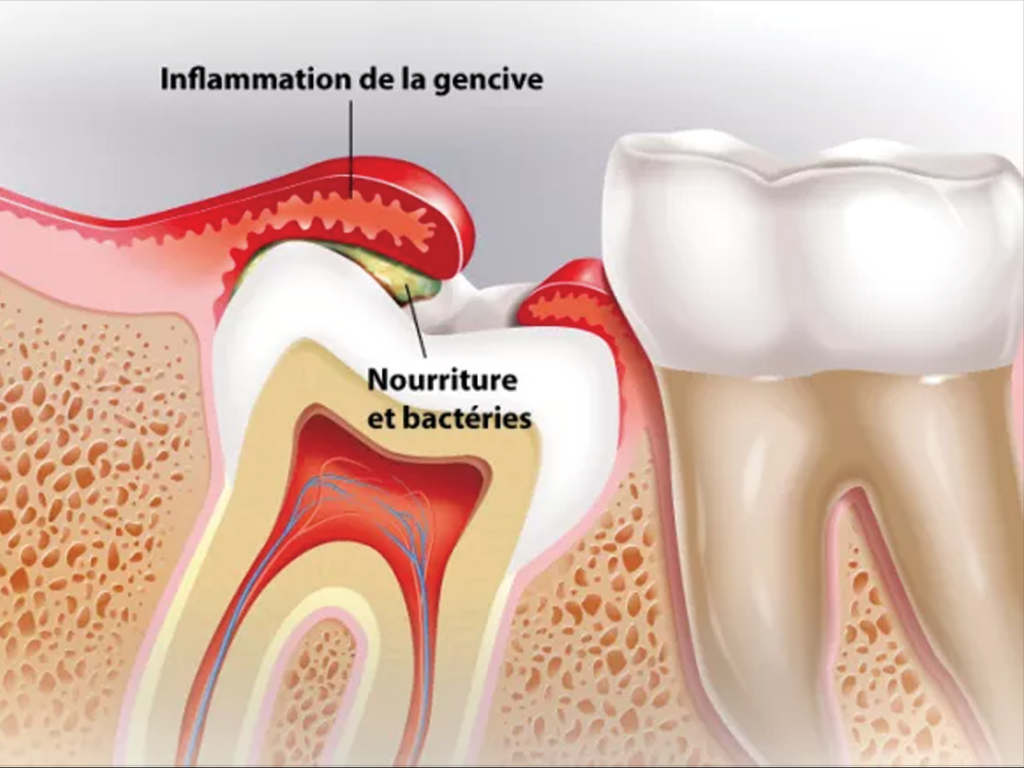

Extraction dentaire

Retrait d’une dent non conservable (carie profonde, fracture, infection) afin de soulager et prévenir les complications.

- Une dent très abîmée, cassée ou infectée (abcès, gonflement)

- Une douleur persistante ou une infection qui revient